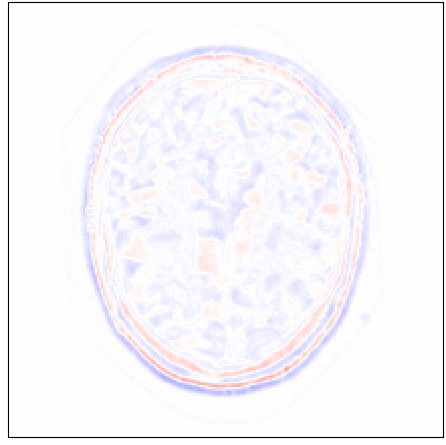

Figure 4: Qualitative evaluation of reconstruction performance of our method on cardiac cine MRI (ACDC dataset). (a) Original cardiac MRI scan; (b) Its reconstruction and (c) Differences between original (minuend) and corresponding reconstructed (subtrahend) slice. Note that to reconstruct a slice xnsubscript𝑥𝑛x_{n} the mixing coefficient α𝛼\alpha in Equation 1 is set to zero. Blue corresponds to negative and red to positive differences. Image intensities are scaled to a [0,1]01[0,1] range. All difference images use the same color scale [1,1]11[-1,1].

Slice Reconstruction: Results for reconstructed and synthesized slices listed in Table I convey that the proposed approach achieved high reconstruction performance especially in terms of SSIM and PSNR. Figure 4 depicts qualitative results of reconstruction performance for the proposed method on cardiac MRI. The results show that the trained autoencoder can reconstruct high-quality images i.e. input slices. Nevertheless, difference image shown in Figure 4(c) depicts that some high spatial frequency details of the input slice are lacking in the reconstructed slice.